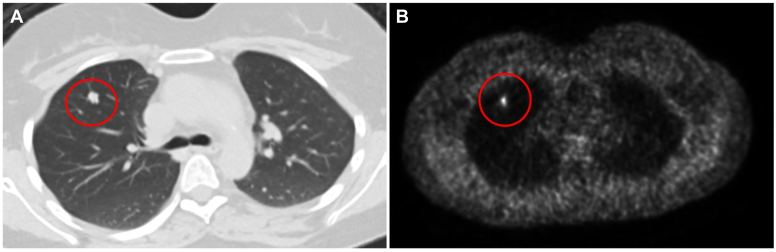

An 18-year-old woman presented with mood disturbances, weight gain, and fatigue for 6 months. Workup revealed high levels of urinary free cortisol (>900 μg/dL; normal range, <45 μg/dL) and midnight salivary cortisol (0.755 μg/dL; normal range, <0.09 μg/dL). The ACTH and cortisol levels remained elevated after a low-dose dexamethasone suppression test. Magnetic resonance imaging of the pituitary gland did not reveal any adenoma and inferior petrosal sinus sampling showed no central-to-peripheral gradient. A diagnosis of EAS was made. Subsequent body imaging noted a 1-cm lung nodule. Due to symptoms of severe hypercortisolism including hypokalemia and worsening mood changes, the patient was started on metyrapone as a bridge to surgery. A few weeks later, the patient underwent successful surgical resection, after which symptoms promptly resolved. Pathology report later confirmed an atypical lung carcinoid tumor. The patient remained in remission at 1-year follow-up.